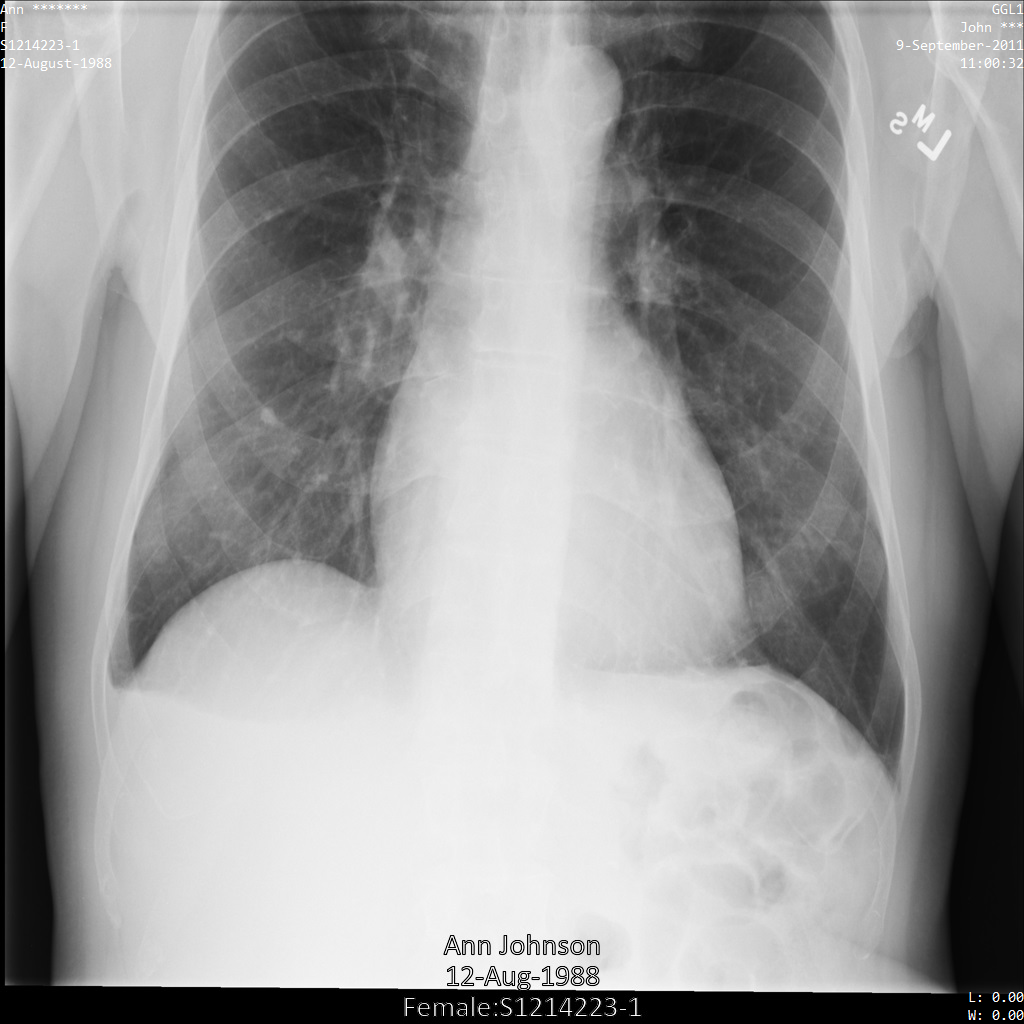

以下各部分提供的示例展示了如何使用各种方法对 DICOM 数据进行去标识化。每个示例都会提供去标识化后的图片输出。每个示例都使用以下原始图片作为其输入:

您可以将每个去标识化操作的输出图片与该原始图片进行比较,以查看该操作的效果。

将图片提交到 Cloud Healthcare API 后,图片显示如下。虽然图片顶部角落显示的元数据已被遮盖,但图片底部的烧屏受保护健康信息 (PHI) 仍然保留。如需一并移除烧屏文字,请参阅遮盖图片中的烧屏文字。